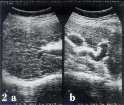

УЗИ цирроз